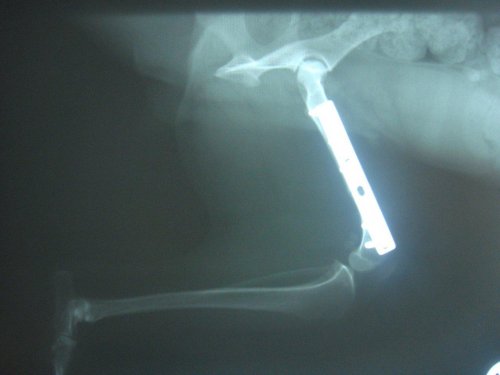

Alle Welpen wurden vermittelt und Tilly wurde am 21.12.2012 bei Dr. Rumpf operiert. Sie hatte einen alten Oberschenkelbruch im linken Hinterbein.

Die OP ist gut verlaufen, Tilly hat eine Platte bekommen und muss im September 2013 nochmals operiert werden. Dabei wird die Platte dann wieder entfernt.

Da der Bruch vermutlich schon mind. ein halbes Jahr alt war, musste bei der OP bei beiden Knochenenden 1,5 cm abgeschnitten werden. Dadurch ist ihr linkes Hinterbein nun verkürzt und Tilly wird immer humpeln. Aber mittlerweile verwendet sie ihr Bein schon wieder mehr.

Ein Kontrollröngten im Jänner 2013 zeigte, das alles in Ordnung ist.